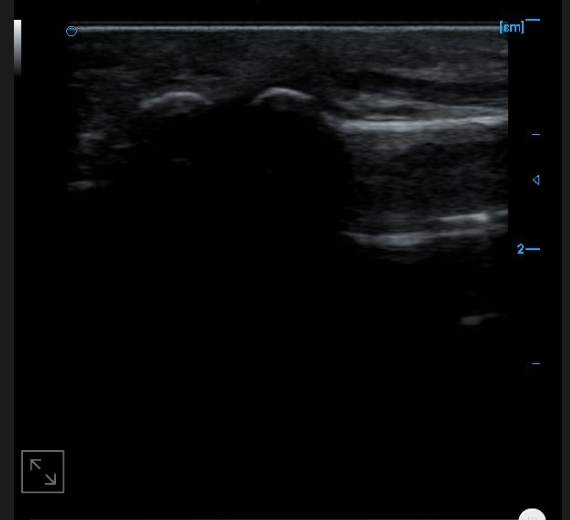

B-image of the anterior cross-section of the upper arm

Cross sectional B-image of the distal tendon of the biceps brachii muscle

B-axis imaging of the distal tendon of the biceps brachii muscle

B-image of upper forearm cross-section